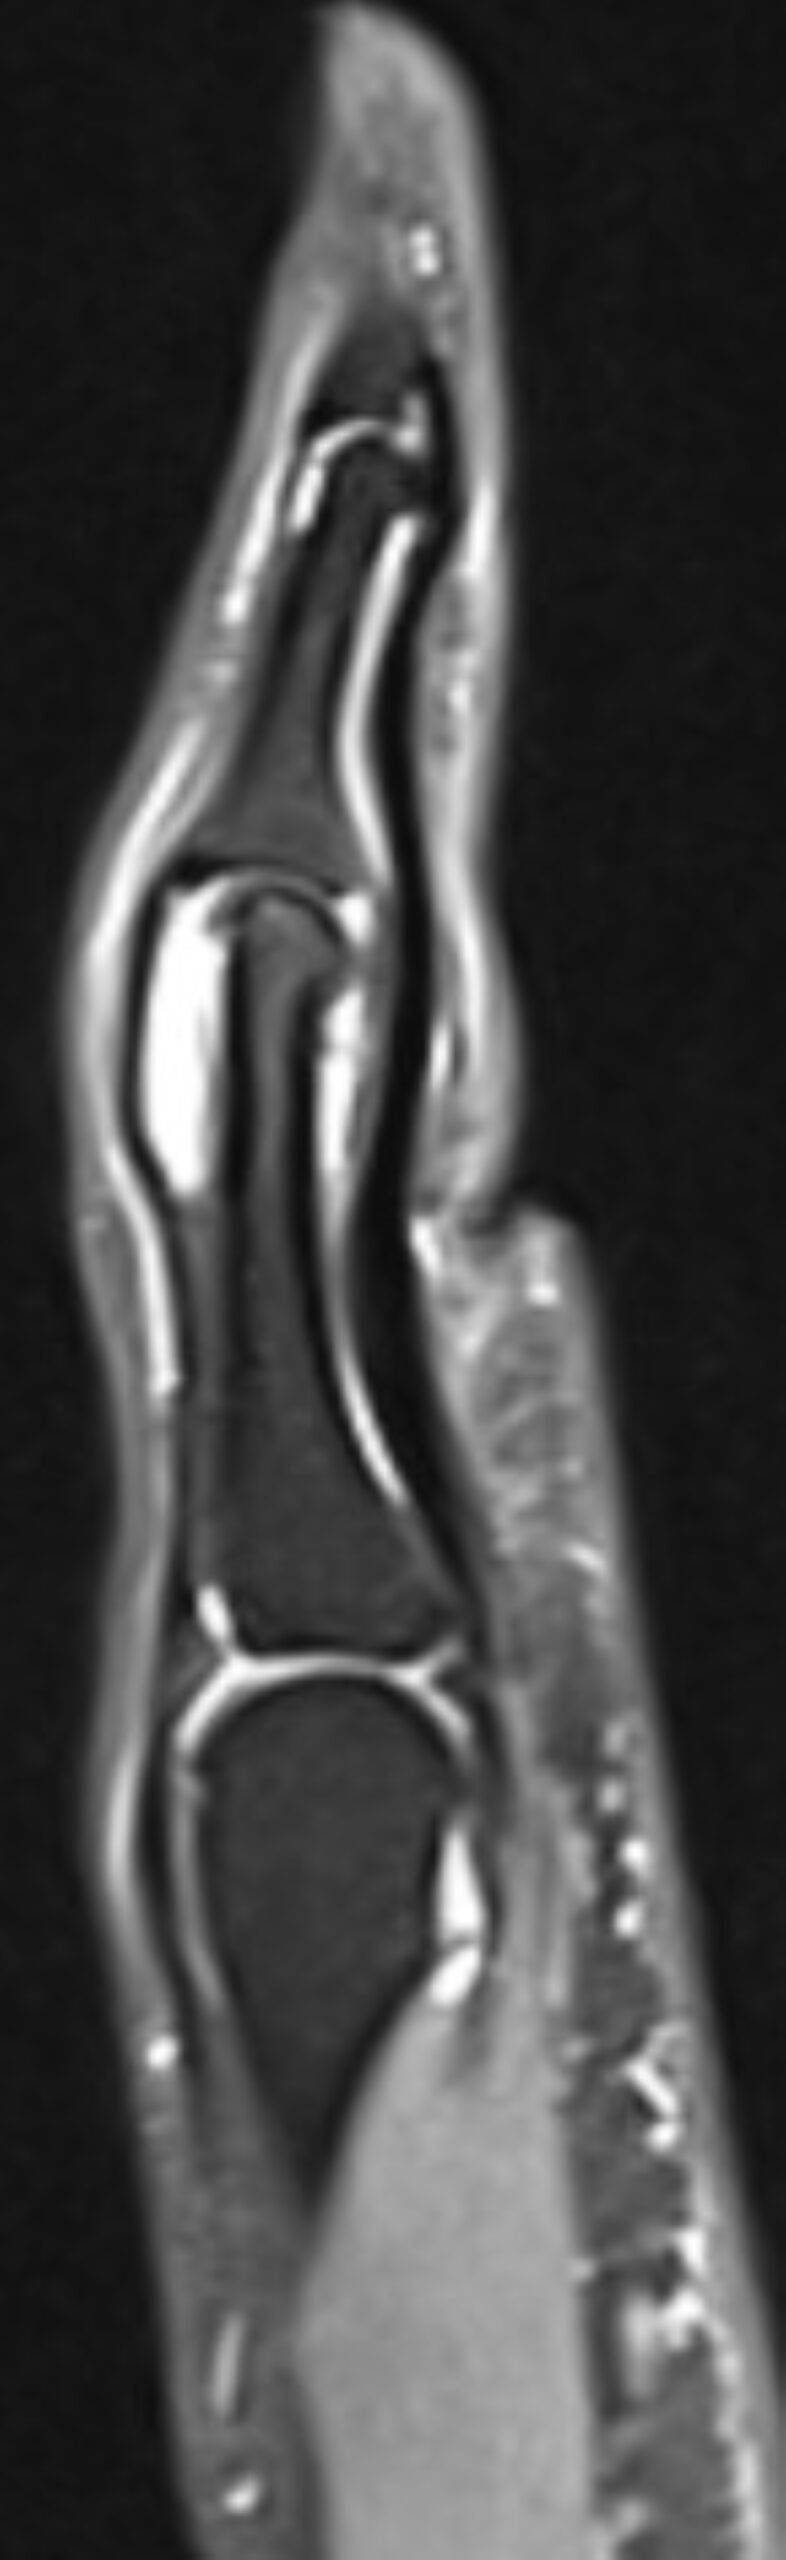

Was sieht man bei einer MRT der Hand?

Eine MRT der Hand liefert detaillierte Bilder aller vorhandenen Strukturen, darunter Knochen, Knorpel, Muskeln, Sehnen, Bänder und Nerven. Eine Hand MRT ermöglicht das Erkennen von Entzündungen, Schwellungen, Flüssigkeitsansammlungen, Rissen und anderen strukturellen Veränderungen und ermöglicht durch hochwertige Bildauflösung eine präzise Diagnose.

MRT Hand Bilder